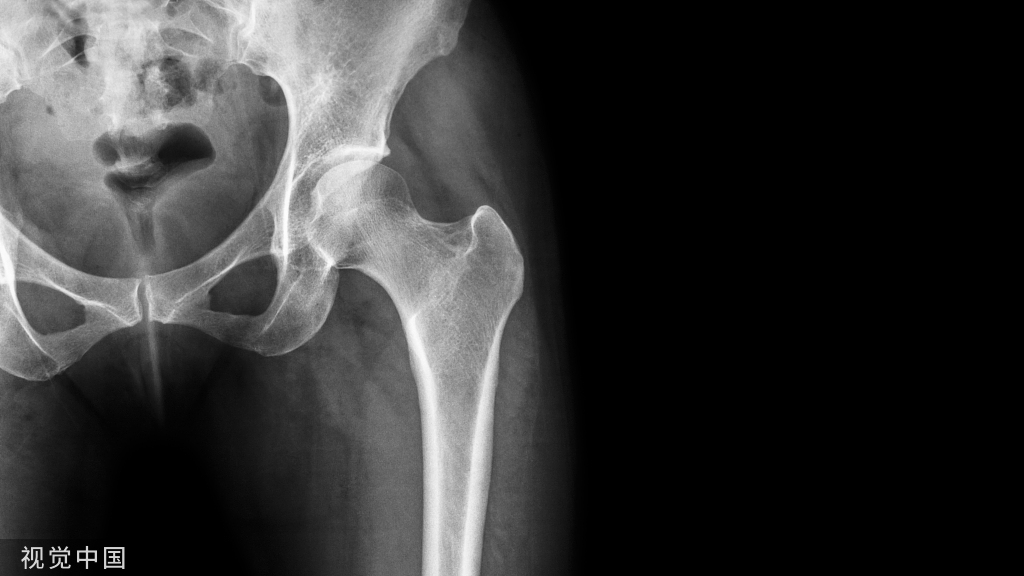

干骺端长斜形骨折采用髓内钉固定的难点之一为骨折对线的恢复,由于骨折暴力因素或骨折周围肌肉的牵拉,断端间通常存在侧方移位趋势,在髓内钉置入时如何纠正骨折断端对位对线是临床较常见问题。

Poller螺钉可以改变髓内钉方向、纠正骨折侧方移位,在长斜形骨折的髓内钉固定中使用越来越广泛。如何有效置入Poller钉,将Poller钉置于何处,显得尤为重要。既往对Poller钉置入存在诸多迷惑之处,如将Poller钉置于“不想让髓内钉去的地方”或者依据“两短原则”等,无明确理论支撑。

为此,有学者描述了一种Poller钉置入位置的原则及操作方法,结果发表在Injury期刊。